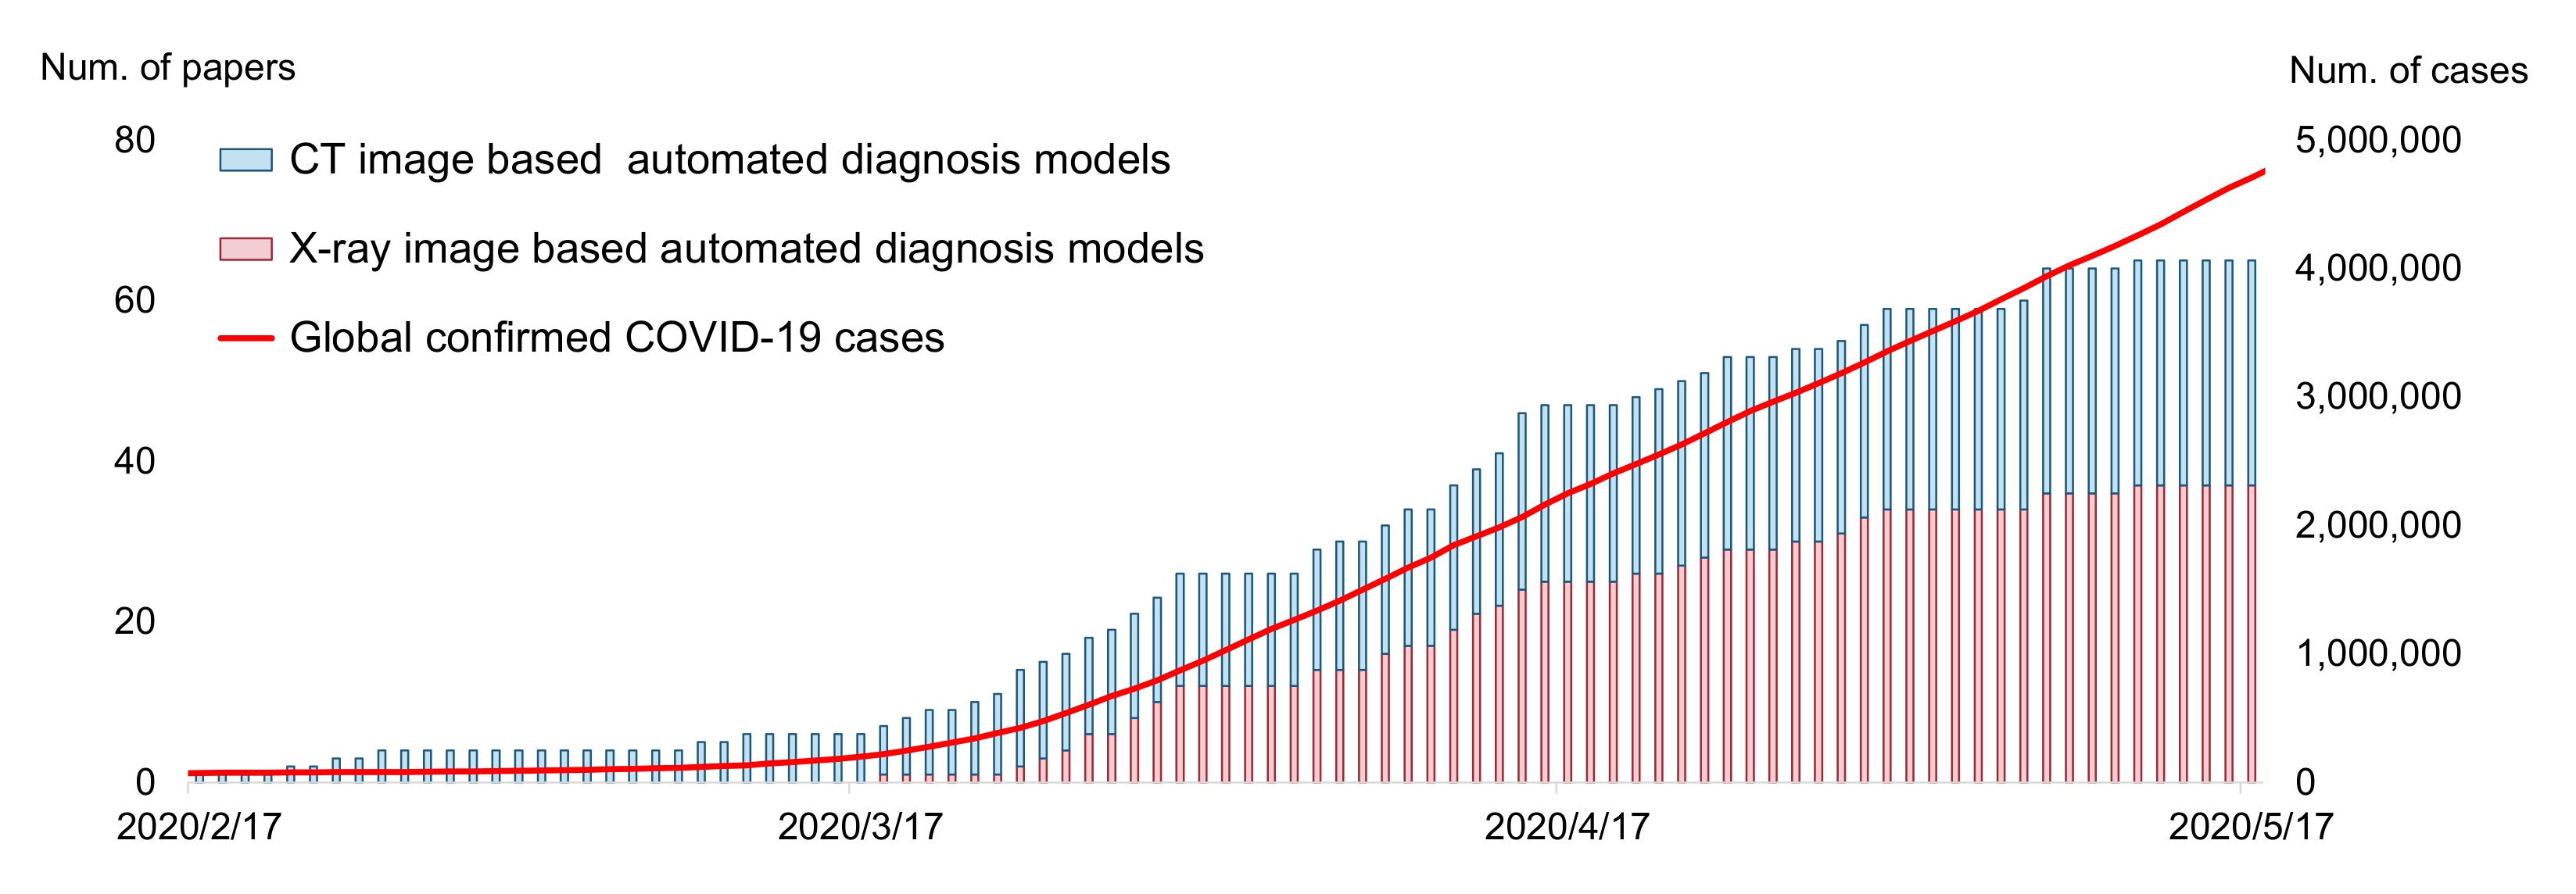

:1. Introduction

2. Input Modalities: CT or X-ray

2.2. Artificial Intelligence Perspective